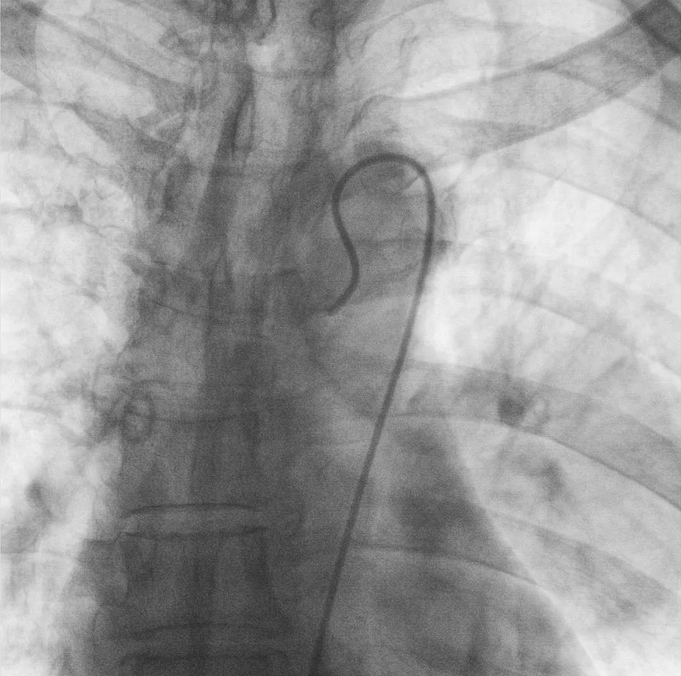

支氣管動(dòng)脈栓塞+化療灌注術(shù)

在普愛醫(yī)療移動(dòng)式平板介入中C影像的引導(dǎo)下,醫(yī)生為患者實(shí)施雙側(cè)支氣管動(dòng)脈栓塞+化療灌注術(shù)。

在微導(dǎo)絲的配合下,先后分別超選擇①至3支左側(cè)支氣管動(dòng)脈腫瘤供血?jiǎng)用},經(jīng)微導(dǎo)管推注栓塞微粒球栓塞腫瘤動(dòng)脈。栓塞結(jié)束后,再次用移動(dòng)式平板介入中C做造影檢查,見腫瘤染色消失。